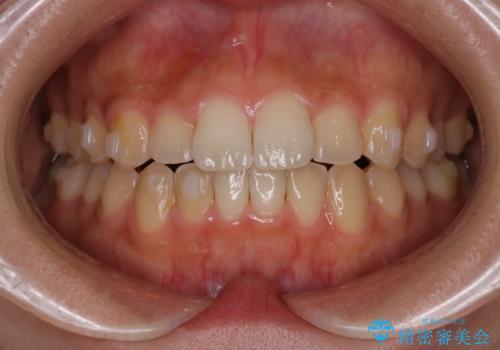

【インビザライン】がたつきをマウスピースできれいにしたい

- 20代女性

- 前歯の叢生を主訴に来院されました。非抜歯でインビザラインで治療をしました。

叢生はIPRをし、並べました。この患者様はオープンバイトだったため歯を並べる過程でかみ合わせも治しました。